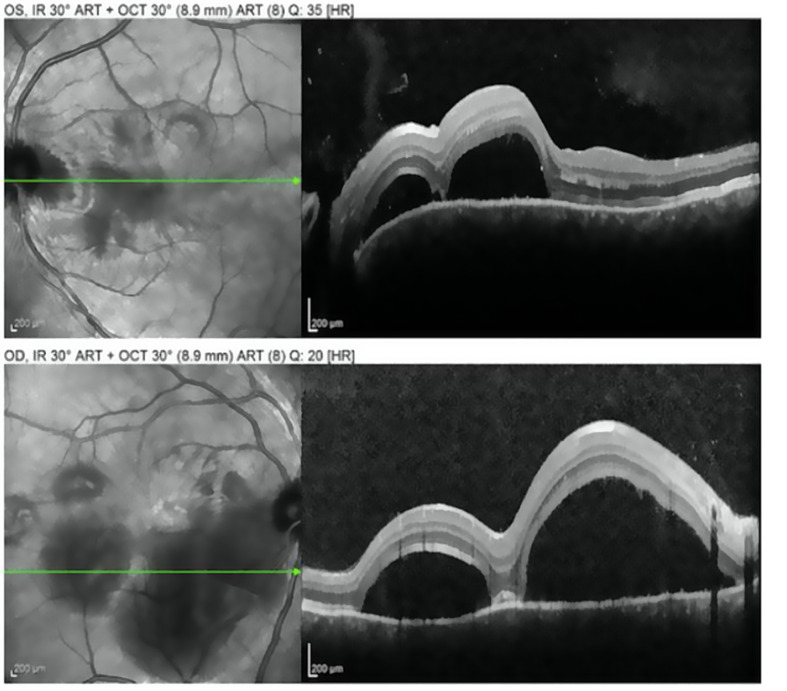

Retrospective analysis of Vogt-Koyanagi-Harada's recurrence within a case series of nineteen patients followed between 2003 and 2018 in an academic center.